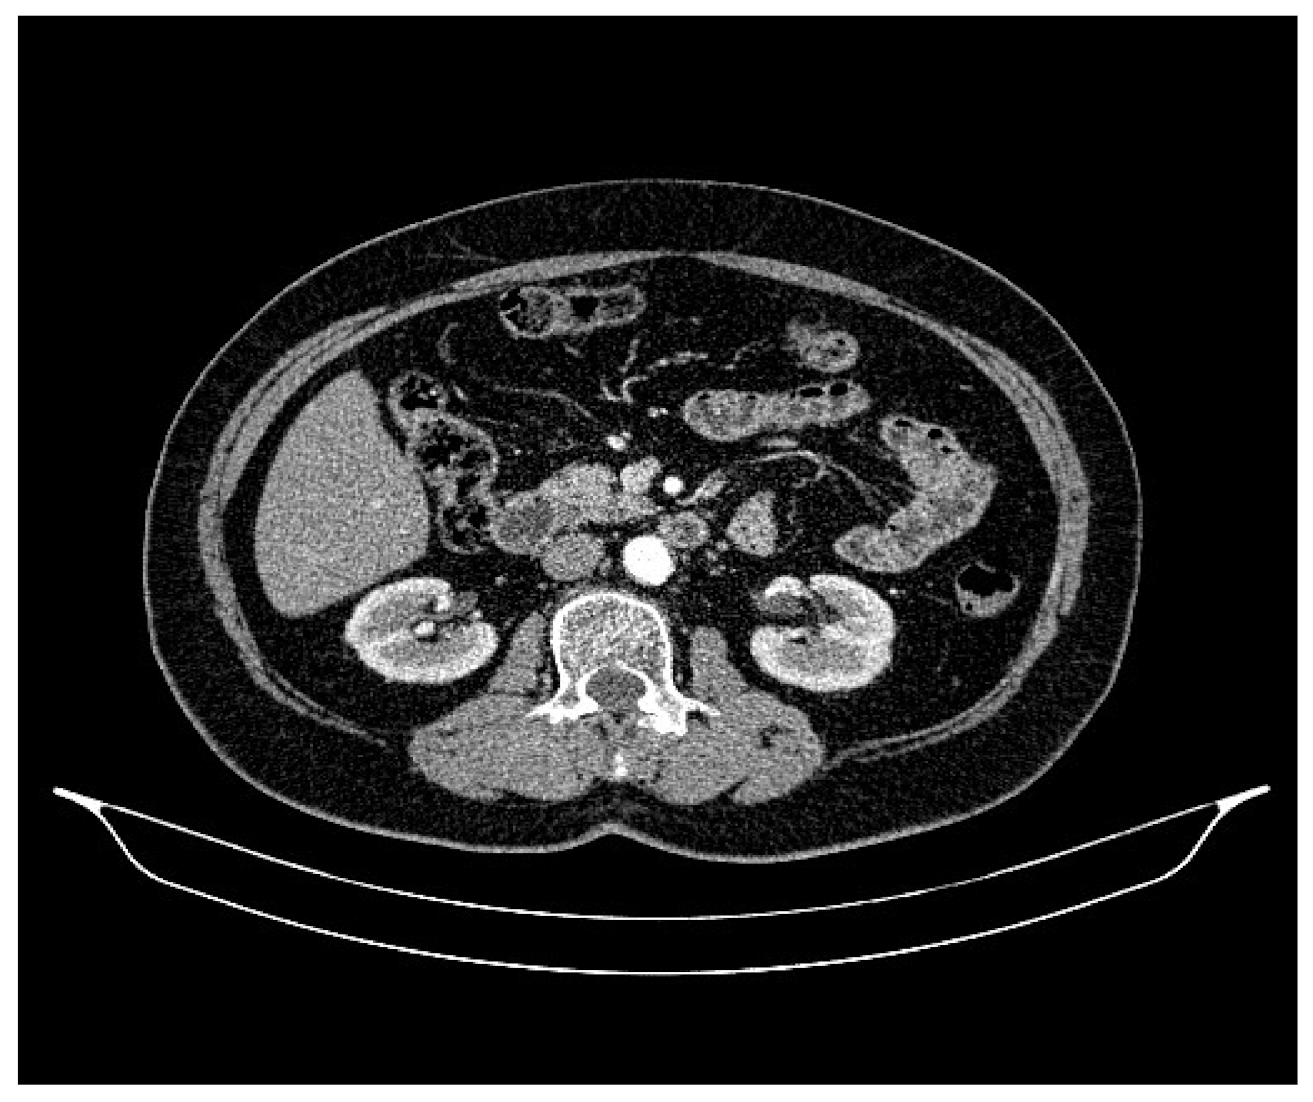

2. Case Presentation